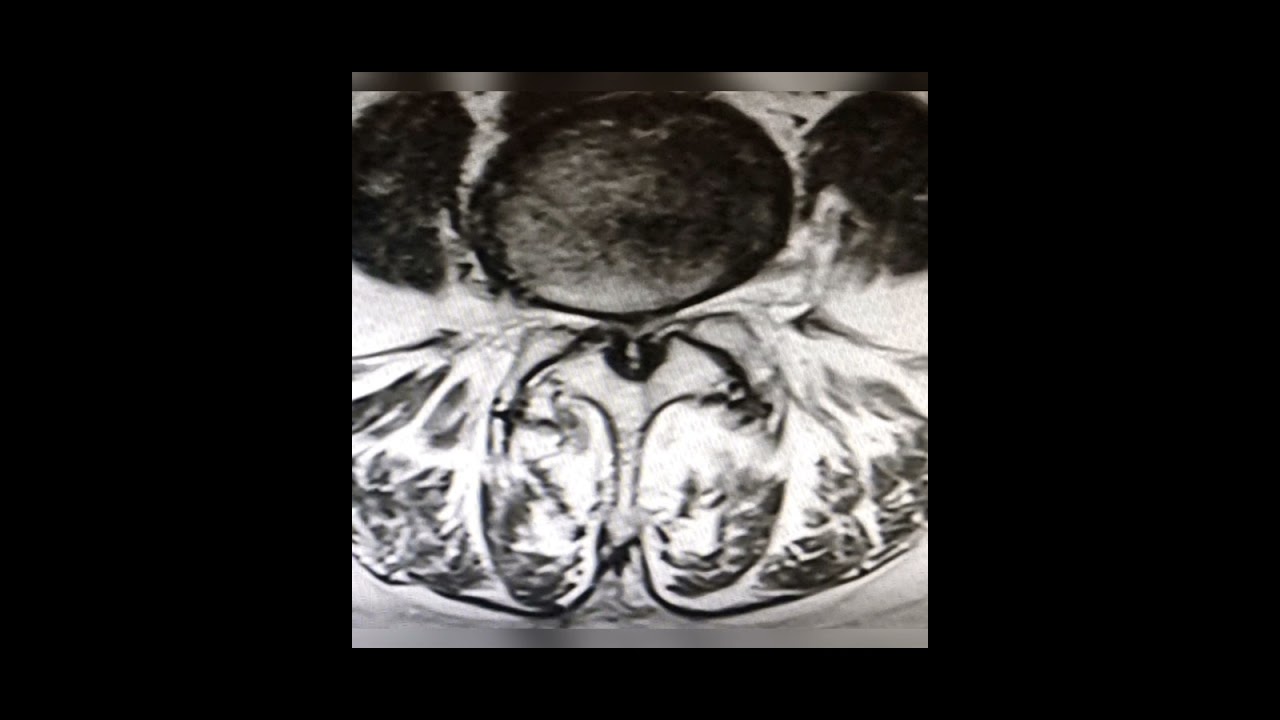

A hérnia de disco ou hérnia discal constitui-se na projeção da parte central do disco intervertebral (o núcleo pulposo) para além de seus limites normais (a parte externa do disco, o ânulo fibroso). O disco intervertebral é uma placa cartilaginosa com a função de "amortecedor" entre os corpos vertebrais. A hérnia pode acometer a coluna dorsal, cervical e lombar. Em torno de 90% das hérnias discais, o tratamento é conservador, sendo necessária cirurgia em apenas 10% dos casos. O índice de satisfação com tratamento cirúrgico é de 90%. Procure um neurocirurgião para melhor avaliação e tratamento.

A síndrome da cauda equina é uma indicação cirúrgica de urgência, pois causa anestesia em sela (entre ânus e vagina ou testículos), claudicação intermitente por déficit motor ( mancar após certa distância de caminhada) e disfunção esfincteriana ( descontrole da urina e evacuação). Neste caso, a não resolução em tempo hábil pode trazer sequelas irreversíveis.

Normalmente as indicações cirúrgicas são déficits motores progressivos (perda de força nos membros), falha no tratamento clínico após 6 a 12 semanas de tratamento, instabilidade na coluna. Apenas 10% dos pacientes com hérnia de disco lombar irão necessitar de cirurgia. É importante haver uma correlação precisa entre a dor (Axial/dermátomo) e o nível a ser abordado. Várias técnicas cirúrgicas são utilizadas para tratamento da hérnia de disco, desde técnicas menos invasivas ( percutâneas e endoscópicas), microdiscectomia e até mesmo artrodese ( se houver sinais de instabilidade). Obs: Axial = dor no meio da coluna, dor em dermátomo= dor que irradia em trajetos específicos na perna.